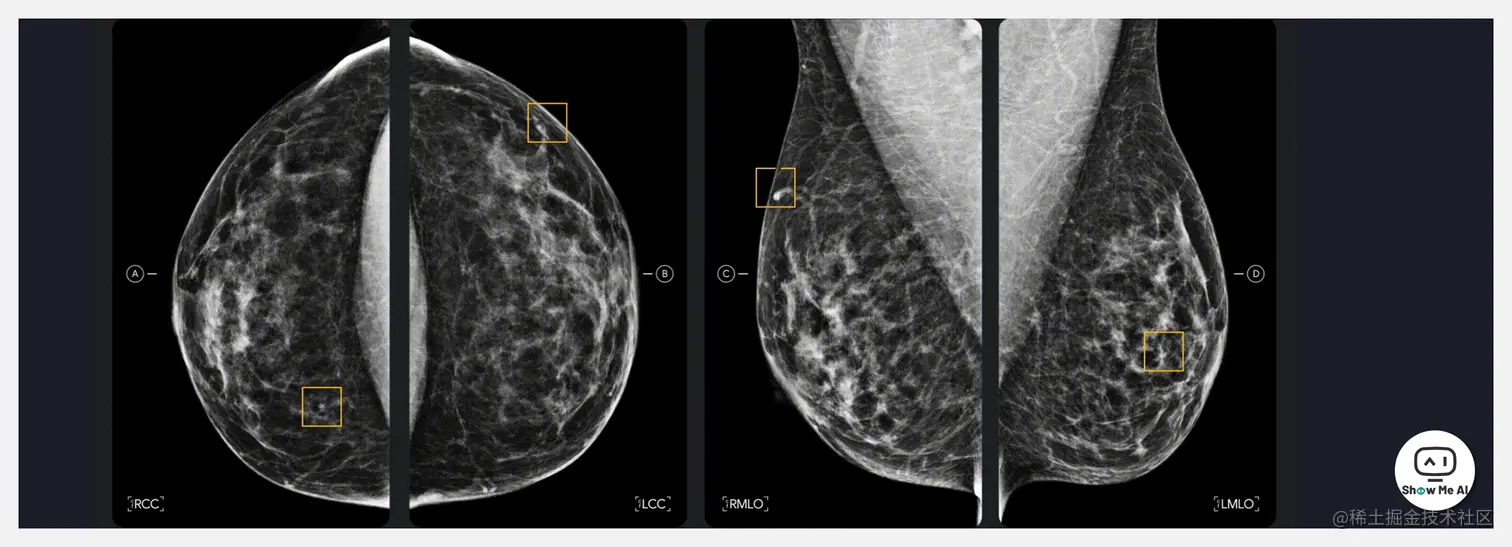

🔥 『Google · Breast Cancer Screening』谷歌与癌症检测领导者 iCAD 合作,推进乳腺癌筛查的临床实践

Google Health 宣布与 iCAD(医疗技术和癌症检测领域的领导者)建立合作伙伴关系,许可将谷歌的“乳腺X线影像AI研究模型”整合到现实的临床实践中,每年为全球超过 200 万被乳腺癌患者提供的癌检测和短期个人癌症风险评估。

乳腺癌是世界上最常见的癌症之一,值得庆幸的是,及早发现可以帮助挽救生命并改善患者的预后。iCAD 的乳腺成像工具组合和 Google Health 的乳腺X线影像AI技术,可以提高乳腺癌筛查的准确性和可用性,缓解放射科系统不堪重负的现状,并使得医生有更多时间为患者提供诊疗方案。